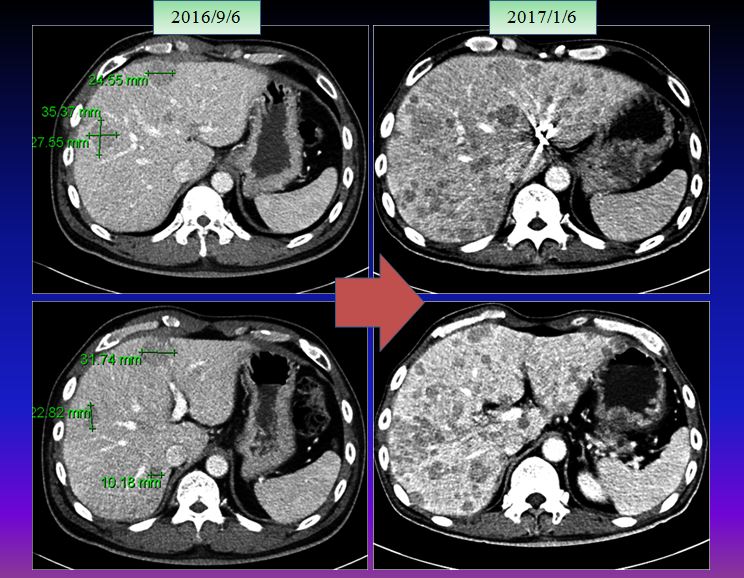

47세의 남자인 이 환자는 젊어서부터 담배를 피기 시작하였는데 20년간 거의 하루 한 갑이상을 피웠고 최근에 경제사정이 나빠지자 스트레스로 하루 2 갑씩을 피웠다고 한다. 그런지 1년이 되어서  복통을 느껴서 검진 결과 간암(hepatocellular carcinoma)으로 복부에 임파전이가 있고 여러 개의 작은 암덩이와 함께 제일 큰 간암의 크기는 약 11cm 정도로 판명되었다(2016/7/9).

이후 8월 7일 MR상 거의 간의 우엽에 14cm 가까이 되는 종양이 보이는데 그 사이에 암이 3cm 이상 자랐다는 이야기가 된다. 이후 K 의료원에서 넥사바라고 불리우는 sorafenib을 2달 동안 사용하였다. 이후 결과는 간의 종양은 약간 자랐다고 볼수 있고 간암의 수치는 많이 떨어졌다고 하였다.

가족들은  간암의 수치가 좋아져서 간의 종양도 많이 줄었을 것으로 기대하였으나 크기는 오히려 약간 커지는 경향을 보이자 많이 실망을 하였고, 이후 주치의는 소음인약인 5-fu. leucovorin.cisplatin 등 folfox 공식을 사용하여서 2016년 11월부터 12월까지 한 달간을 사용하였다.

이후 주치의는 folfox 공식에 준하는 cisplatin 5-fu. leucovorin을 결합 사용하였는데 이는 모두 소음인 약물로 소음인에게는 유효하지만 태음인에게는 반응을 하지 않거나 더 빨리 암을 진행시킬 수있다. 암은 유지시키는 것만으로도 중요한데 암 크기가 다소 늘어났다고 하여서 소음인 약으로 바꾸고 나서 결국은 매우 악화되어서 며칠 전 본원에 내원하였다. 이를  비교해 보면 다음과 같다.

9월 사진만 해도 약간씩 증가된 것으로 보이는데 한 달간 소음인 약물로 추론되는 항암제를 사용하고 나서 간 전체가 무수히 많이 보이는 점들로 꽉 차게 되었다. 여기다가 또 무슨 약침이니 하는 요법을 하는 도중에  본원에 내원하게 되었다. 환자는 나이가 아직 젊다는 것 빼놓고는 무엇하나 건질 것이 없는 정도로 상태가 나빴지만 어느 한의사 선생님이 소개해 주어서 내원하였다 한다.